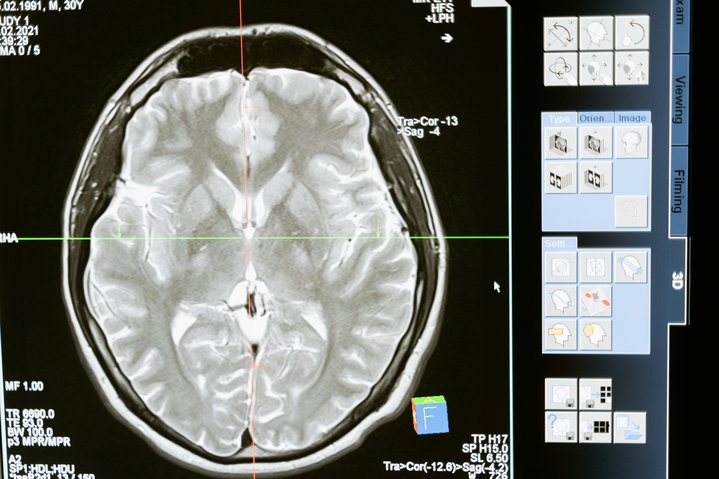

Partindo dessa premissa, os pesquisadores decidiram conduzir um estudo para tentar resolver essa lacuna. E eles descobriram que algumas das respostas podem estar dentro de uma tomografia cerebral.

Todos eles foram submetidos a um exame de imagens chamado ressonância magnética funcional (ou fMRI), para medir a atividade cerebral.

Na sequência, os pesquisadores usaram uma abordagem de aprendizado de máquina conhecida como análise de cluster para agrupar as imagens cerebrais dos pacientes.

Foi aí que eles identificaram seis padrões distintos de atividade nas regiões cerebrais que estudaram.